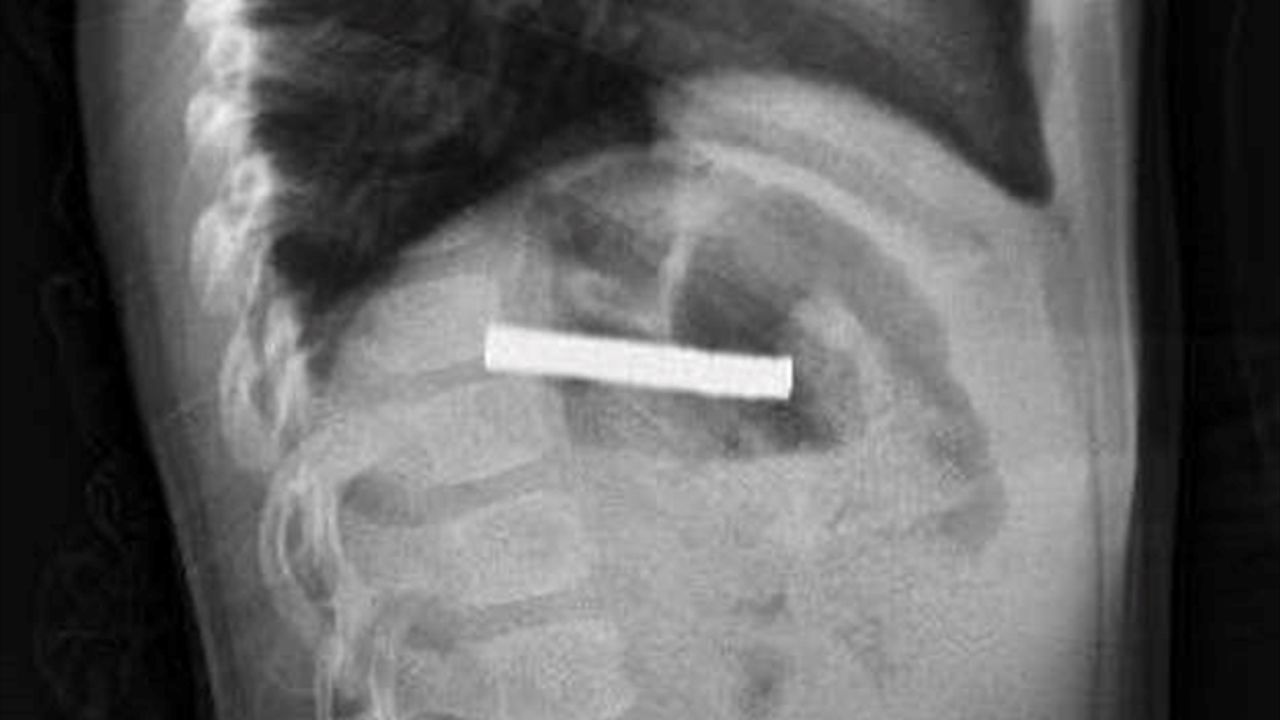

Hastanede, FÜ Çocuk Gastroenteroloji Hepatoloji ve Beslenme Bilim Dalı Başkanı Prof. Dr. Yaşar Doğan tarafından yapılan tetkiklerde mıknatısların yapışarak çocuğun yemek borusunu tıkadığı tespit edildi.

Yapılan operasyon hakkında bilgi veren Doğan, 'Tabi bu mıknatıslar uzun süre hastanın yemek borusunda kaldığı için biraz hasar bırakmıştı. Çok güçlü mıknatıslardı. İşlemin kolay yapılabilmesi için mıknatıslar yemek borusundan mideye alındı, mideden özel bir fileyle çıkarıldı. İşlemden sonra hastayı gece boyunca gözlem altında tuttuk. Sabah da aile kendi isteğiyle çıkarmak isteyince, hastanın da genel durumu iyi olduğundan taburcu ettik.' dedi.